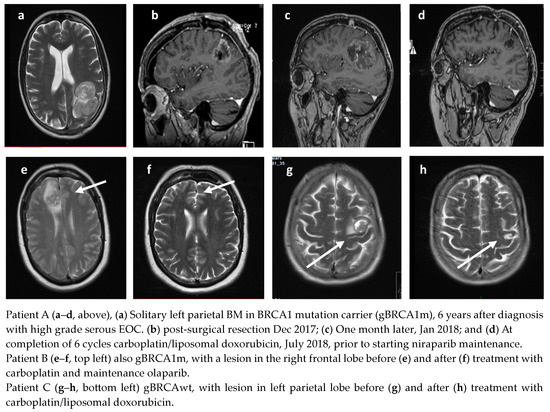

A total of 35 patients received treatment for BM. The median time to BM from the end of first-line treatment for BRCAm patients was 21.5 months (range 8–42), and 23 months (range 16–27) for BRCAwt patients. BM as the only site of first relapse occurred in 14 patients (BRCAm n = 7 and BRCAwt n = 7). Thirteen of these patients had an initial remission of greater than 1 year (13–52 m) prior to their relapse with BM. Systemic treatments were not planned for five of these fourteen BM patients, although one patient responded well to chemotherapy having progressed within six weeks of surgery (Figure 1). A total of 7/14 patients (three BRCAm) had further relapse(s) following treatment, with a median PFS of 13.5 months (2–25 months). At the time of analysis, 6/14 (four BRCAm) remain in remission, with a median PFS of 37 months (10–64 months), following treatment for BM. Four remain on PARPi. Examples of patients are demonstrated in Figure 2a–h.

Figure 2.

Radiological responses of three patients with BM on PARPi therapy (arrows denote sites of brain metastases).

Patient A, with gBRCA1m, was diagnosed with a solitary BM 42 m after initial diagnosis (Figure 2a). The left parietal lobe mass was surgically resected (Figure 2b), but she presented one month later with deteriorating neurology; her performance status had declined to three. Repeat MRI demonstrated early recurrence in the surgical bed and a new right parietal metastasis (Figure 2c). She was treated with six cycles of carboplatin/liposomal doxorubicin followed by maintenance niraparib; she remains in complete remission (CR) over 36 months later and is still taking niraparib (Figure 2d). Patient B, also gBRCA1m, was treated with carboplatin and maintenance olaparib (Figure 2e,f). Patient C, gBRCAwt, received caboplatin/liposomal doxorubicin and maintenance niraparib (Figure 2g,h).